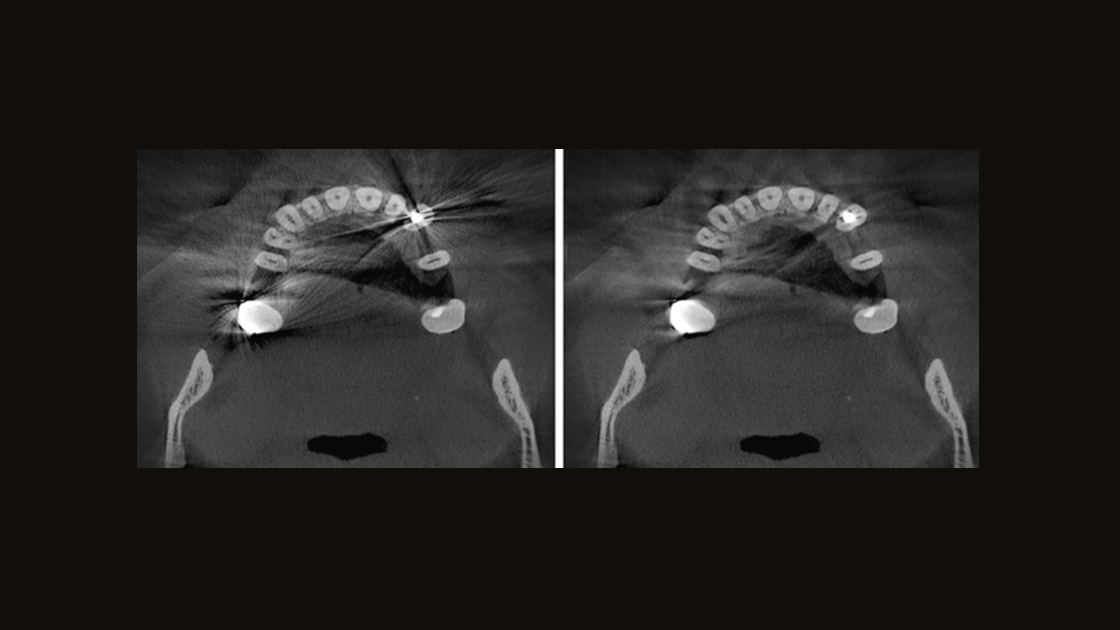

Improve the oral health of your patients by having the ability to diagnose and plan treatment for nearly all etiology in the dentomaxillofacial region. DS X-ray solutions support patient needs from capturing the temporomandibular joints to visualizing the smallest details using up to 80 µm high-resolution endodontic X-ray.